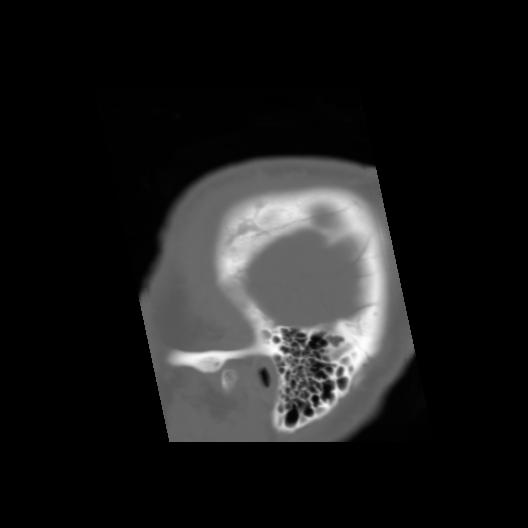

6 CEREBRO,,Sagittal,3.000,CEREBRO,Sagittal,